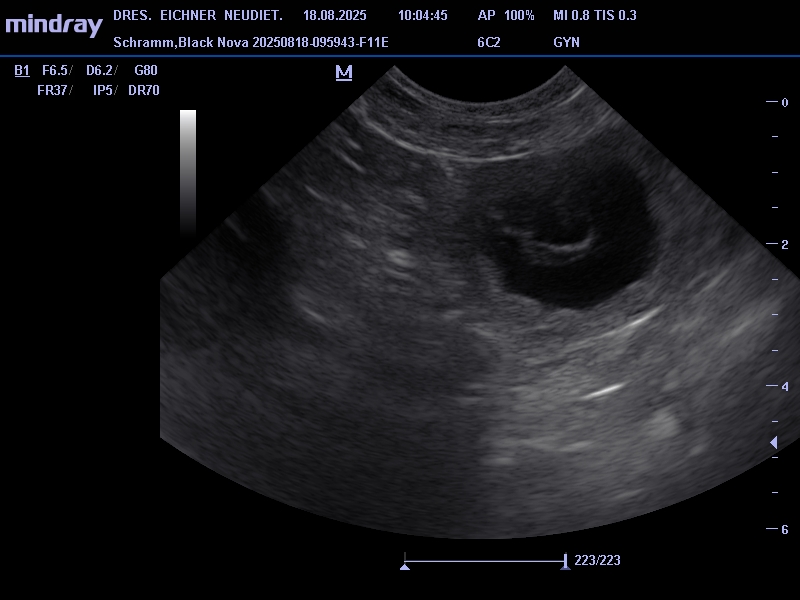

Unsere jüngsten Hündin Black Nova hatte ihr erstes Date mit Pepe am 19. 07. 2025. Pepe ist ein kräftiger kompakter Rüde mit sehr guten Gesundheitswerten. Die zwei haben sich beim Date und auch schon bei einem vorhergehenden Treffen gleich verstanden. Am 18.07. waren wir dann beim Ultraschall, das Ergebnis war positiv, somit erwarten wir Mitte September kleine Bullis in unseren Kennel. In der Nacht vom 20. zum 21. 09. 2025 sind 7 kleine Apfelknirpse bei uns gelandet, 4 Rüden und 3 Hündinnen. Nova und den Welpen geht es gut alle sind wohlauf. Alle Knirpse haben ihr Zuhause gefunden und sind ausgezogen.